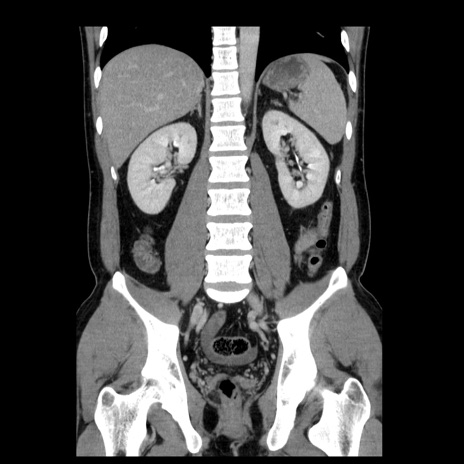

症例4(冠状断像)

【症例】30歳代男性

【主訴】腹痛、嘔吐

【現病歴】昨晩から突然の腹痛あり、その後嘔吐、軟便も出現。腹痛が改善しないため救急搬送となる。2日前にしめ鯖の食事歴あり。

【身体所見】意識清明、苦悶様、BP 135/90mmHg、BT 35.7℃、腹部:平坦、やや硬、心窩部〜臍部に自発痛、圧痛あり、筋性防御+、反跳痛-

【データ】WBC 8100、CRP 0.57